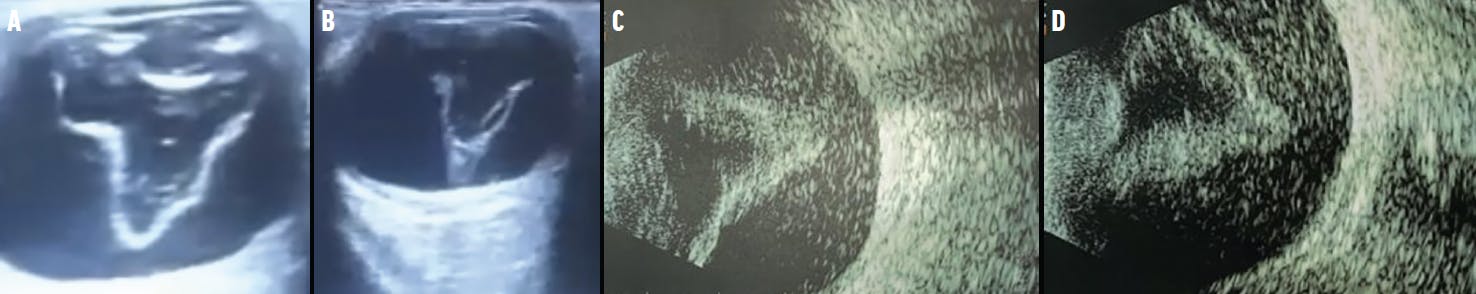

A 52-year-old patient with high myopia and a familial history of RD presented to our clinic. He had undergone two prior surgeries for RD repair. VA was light perception OD. Anterior synechiae and peripheral iris retraction were noted in the anterior segment, signs that point to advanced PVR (Figure 1). Visualization of the retina was impossible, but B-scan ultrasonography confirmed a V-shaped RD (Figure 2).

The clinical evaluation of PVR should always start with an anterior segment examination to help determine the disease stage and inform the next steps in managing this serious complication of RD. If available, B-scan ultrasonography can help confirm findings noted on the anterior segment.